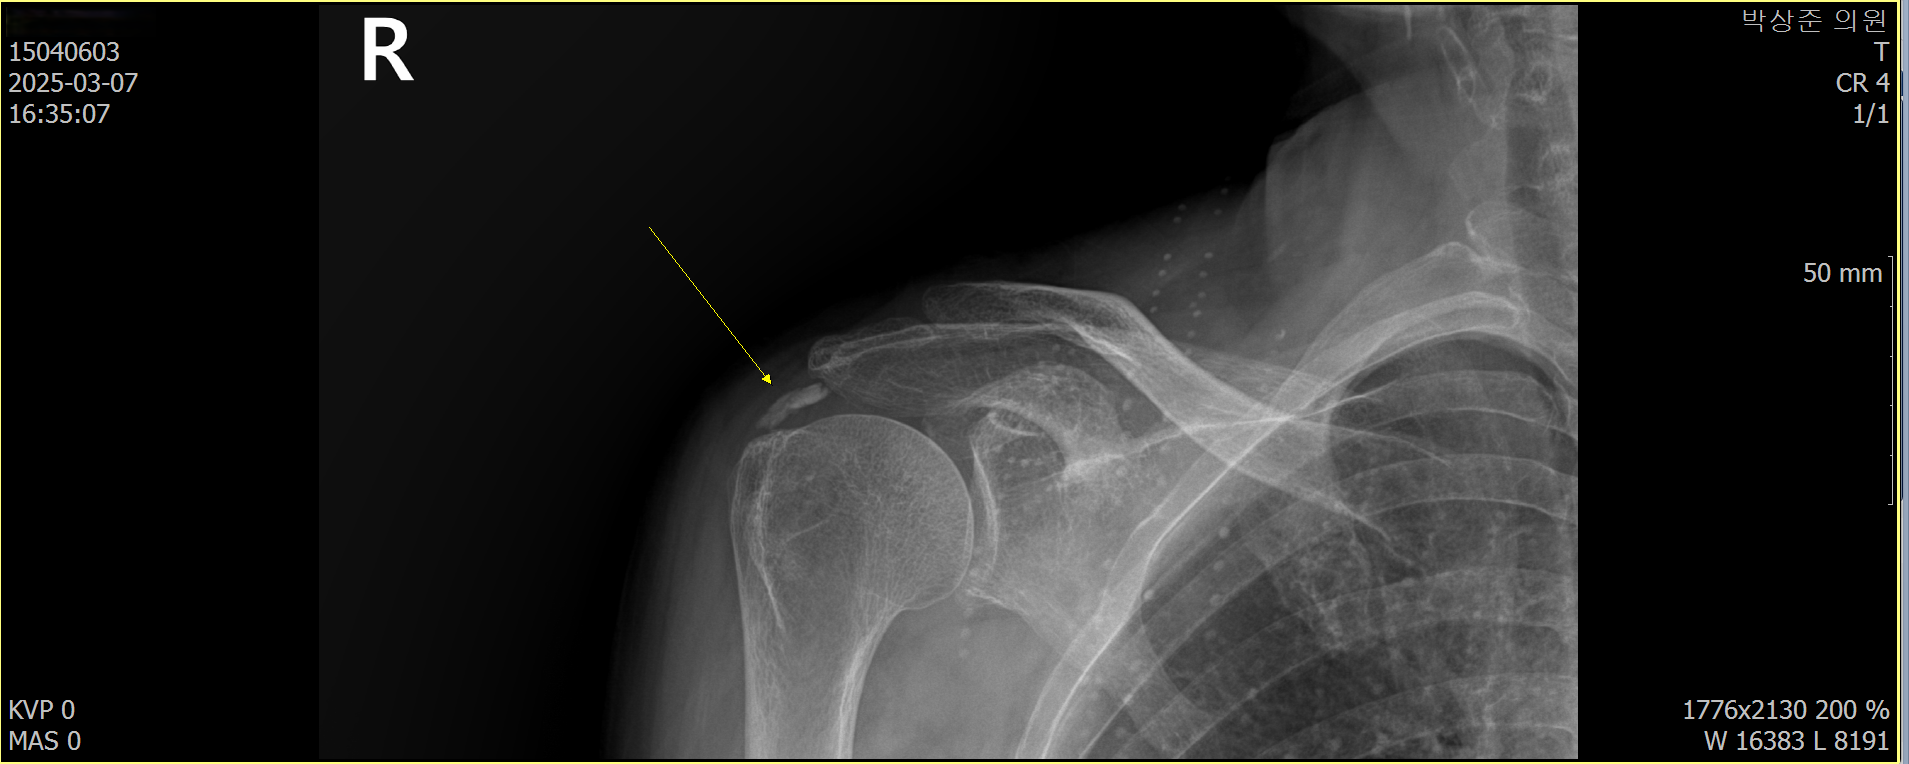

석회성 건염의 경우 사이즈가 조금만 커도 x-ray에서 쉽게 진단이 가능합니다. 이 환자분의 경우 우측 어깨에 사이즈가 꽤 커다란 석회가 관찰되고 있었습니다.

나 : 보시다시피 여기 이렇게 큰 석회가 들어 있네요. 이전에도 이정도로 보였나요?

환자 : 정확히는 기억 안나지만... 비슷한거 같은데...

나 : 그럼 체외 충격파만으로는 치료가 안되는 케이스네요.